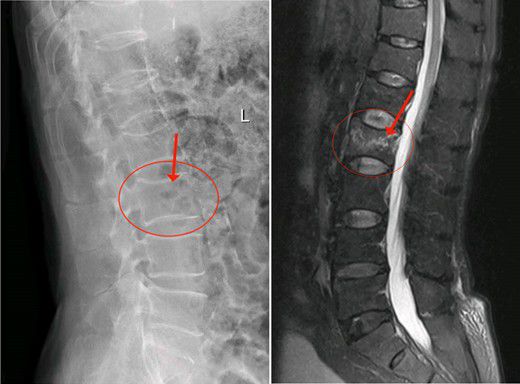

經内科綜合治療後,2月14日陳大伯身體各項指征平穩,可耐受手術。吳主任根據術前方案,爲老人家實施椎體成形術。在我院先進的術中三維CT機引導下,準确将2根穿刺針經雙側椎弓根穿入骨折椎體内,通過穿刺針建立通道注入骨水泥。術中三維CT機監視骨水泥分布良好,順利完成手術。手術切口小,無須縫合。由于采用局麻,術中陳大伯甚至還可以和醫護人員對話。注入的骨水泥支撐起原本空洞的椎體,骨水泥凝固後使病變的椎體迅速恢複了承重能力。

△術後,病變的椎體迅速恢複了功能